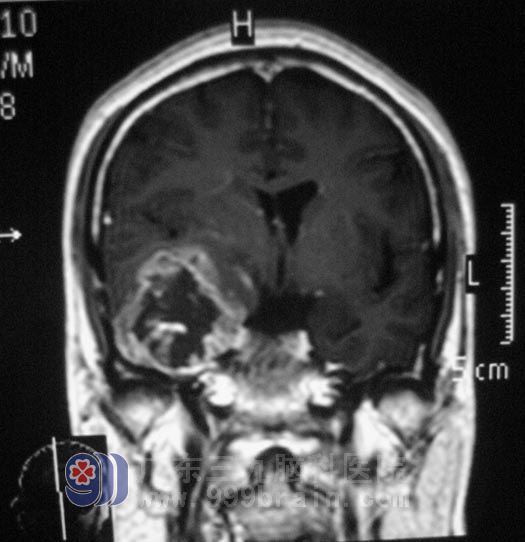

刘先生,今年54岁,在商场的打拼让他连小感冒都没有,一周前无明显诱因突然出现头晕,家里儿子、女婿们以为生意过于操心劳累所致,休息了一个星期也不见好转,于是在外院做头颅CT显示:小脑占位。家里人都不相信这个结果。后来刘先生的儿子在网上搜索到三九脑科医院,找到三九脑科医院神经外五科鲁明主任,经头颅MR检查及专科查体,脑组织受压明显,鲁明主任初步诊断刘先生所患为:右侧颞叶占位,初步考虑为恶性胶质瘤。http://www.999brain.com/

经全面完善术前检查, 5月19日,由鲁明主任主刀,为刘先生在全麻下行右侧颞叶占位切除术,术中见脑组织压力高,颞部灰红色肿瘤组织,肿瘤供血丰富。鲁明主任从容应对,以过人的技术顺利完成了这一例高难度手术。刘先生顺利进入康复治疗期,经过住院治疗,刘先生术后未出现任何并发症,现已经转入放疗科行进一步的治疗。术后经病理结果也证实了鲁明主任的判断是正确的,刘先生脑内所患的是:(右颞叶)胶质母细胞瘤,WHO IV级。http://www.999brain.com/

手术前